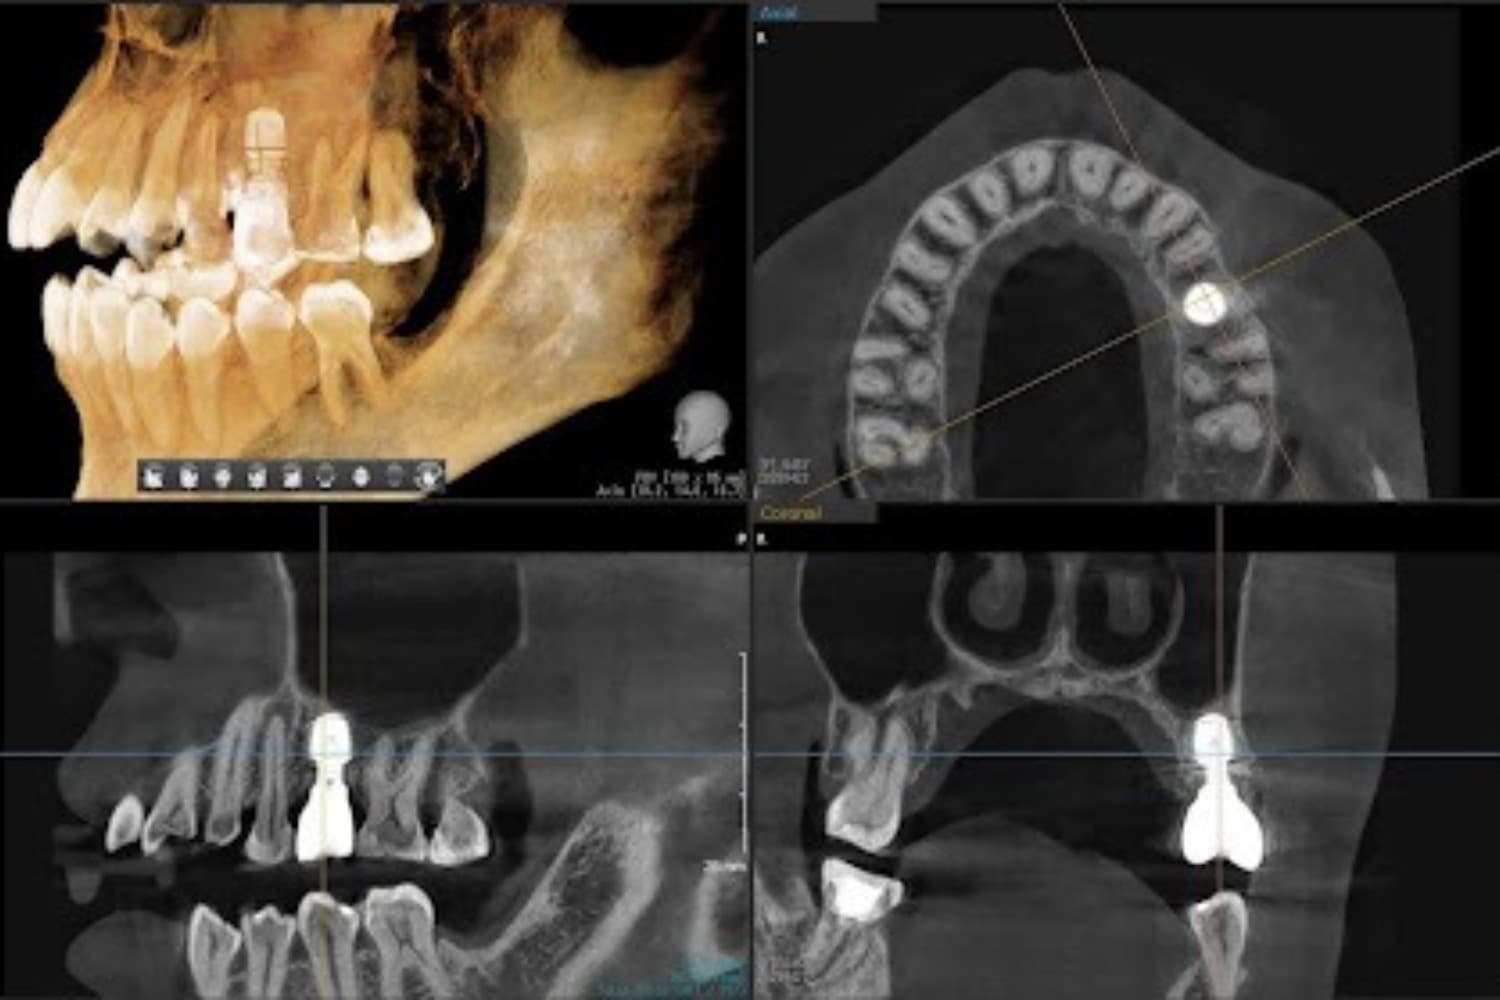

歯根破折した前歯のインプラント治療(30代男性)

Before

After

外傷によって歯根破折した前歯を抜歯してインプラント治療をおこなう(当日に仮歯の装着までおこなう)。

年齢

30代

性別

男性

主訴

外傷によって歯根破折している。

治療期間

2ヵ月半

治療回数

6回

費用

385000円(税込) 費用の内訳: 【インプラント基本料】330000円(税込み) 基本料金に以下を含む ・フィックスチャー及び手術費用 ・投薬費用、 ・レントゲン費用 ・インプラント上部費用(アバットメントおよびジルコニアクラウンの費用用) 【オプション費用】 ・抜歯即時埋入・即時負荷加算(プロビショナルレストレーション費用・人工骨費用・暫間アバットメント費用・抜歯費用を含む)55000円(税込)

副作用・リスク

・手術後に痛み・腫れ・出血・合併症等を引き起こす恐れがあります。 ・噛む感覚がご自身の歯と異なることがあります。 ・見た目がご自身の歯と異なる場合があります。 ・手術後もメインテナンスを続けないと、インプラントが抜け落ちてしまう恐れがあります。